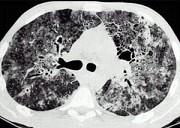

问题 HIV患者咳嗽咳痰一月余,伴发热,结合影像图像,选择最可能的诊断 ( )

选项 A.机会性肺部感染 B.卡氏肺孢子菌性肺炎 C.卡波氏肉瘤 D.肺淋巴瘤 E.间质性肺炎

答案 B